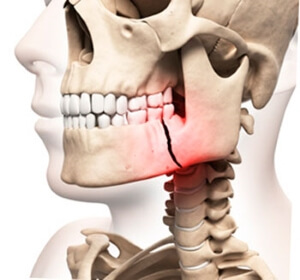

Обладая крупными размерами, челюсть имеет немного выдвинутое положение и наиболее подвержена травмам.

По частоте повреждений первое место занимает перелом суставного отростка. Частым стало травмирование средней части тела нижней челюсти и ее угла.

Различают переломы:

- Закрытые;

- Открытые;

- Полные;

- Неполные.